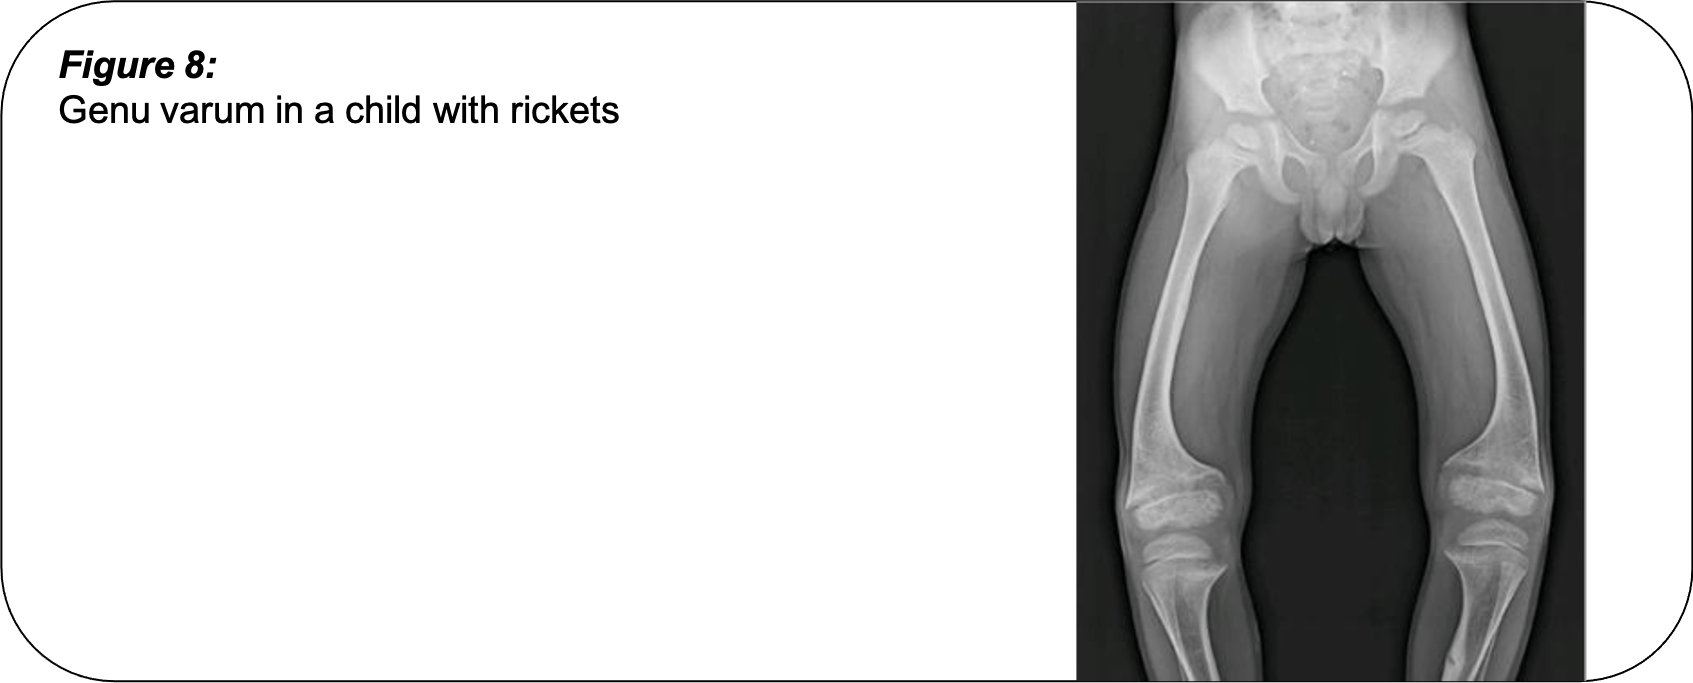

Causes Of Bowlegs . It answers some common questions. Rickets, a bone growth problem caused by lack of. Bowlegs (genu varum) is a condition in which a child’s legs curve outward at the knees. When a child with bowlegs stands with their toes pointing forward, their ankles may touch but their. What causes bowlegs in children? Learn what causes it and how. This article focuses on bowlegs in adults, including teenagers who have reached skeletal maturity (completed growth). How are bow legs diagnosed? It can be a sign of an underlying disease. Bowlegs is a condition in which your knees stay wide apart even when your ankles are together. Bowlegs that do not straighten as your child begins to walk may be caused by more serious problems such as: What are the symptoms of bow legs? What is the treatment for bow legs?

Causes Of Bowlegs Bowlegs is a condition in which your knees stay wide apart even when your ankles are together. This article focuses on bowlegs in adults, including teenagers who have reached skeletal maturity (completed growth). Bowlegs that do not straighten as your child begins to walk may be caused by more serious problems such as: Bowlegs (genu varum) is a condition in which a child’s legs curve outward at the knees. It answers some common questions. When a child with bowlegs stands with their toes pointing forward, their ankles may touch but their. Bowlegs is a condition in which your knees stay wide apart even when your ankles are together. Learn what causes it and how. Rickets, a bone growth problem caused by lack of. What are the symptoms of bow legs? It can be a sign of an underlying disease. What is the treatment for bow legs? How are bow legs diagnosed? What causes bowlegs in children?